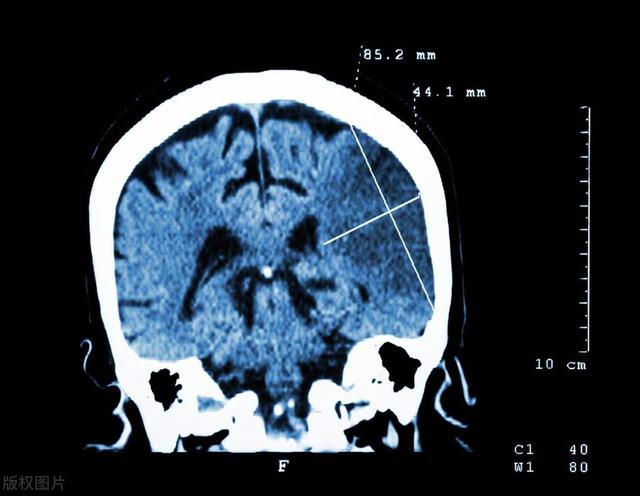

此时 , 刘奶奶的女儿才反应过来拨打了120急救电话 , 又过了十几分钟 , 刘奶奶被送到了卒中中心 , 检查结果提示脑梗 , 医生立即抢救治疗 , 但是由于错过了最佳治疗时期 , 刘奶奶还是落下了半身残疾 。